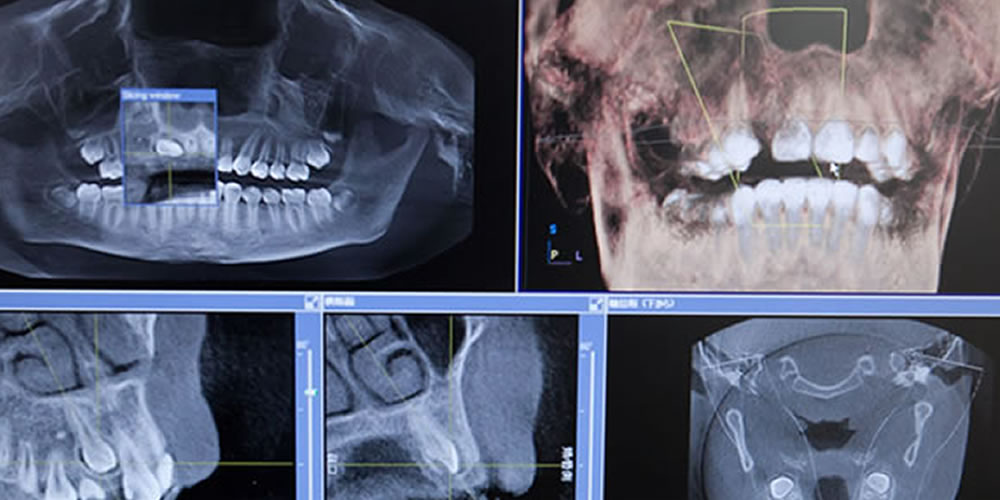

- CT検査による精密なシミュレーション